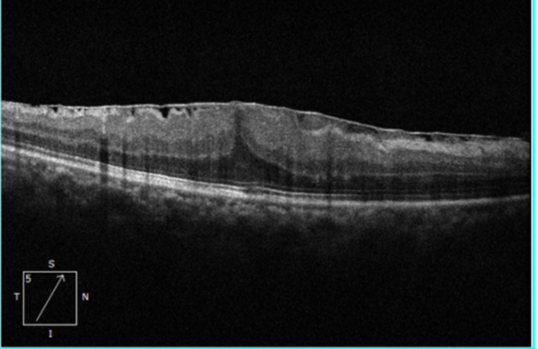

1. OCT(光学相干断层扫描):这是诊断和评估黄斑前膜的「金标准」。它可以无创、高分辨率地「断层扫描」黄斑,清晰显示前膜的存在、厚度、以及其是否导致黄斑水肿、结构层次是否紊乱。OCT 也是监测病情变化和决定手术时机的关键工具。

术前黄斑 OCT 及欧堡:

术后 黄斑 OCT 及欧堡: